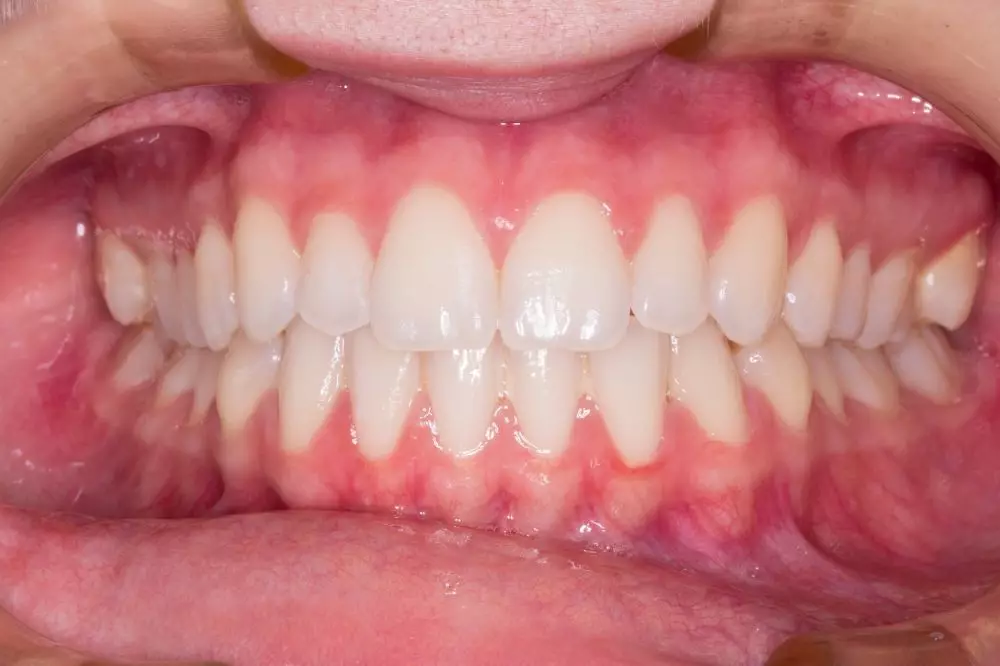

3. Struktur gigi yang tidak rapi

Gigi bungsu yang tumbuh di ruang yang tidak cukup dapat mendorong gigi-gigi lain dari posisi aslinya. Hal ini mengakibatkan gigi menjadi berjejal atau tumpang tindih, yang dapat memengaruhi penampilan estetis serta fungsi pengunyahan. Ketidakrapian ini juga mempersulit kebersihan mulut, karena sisa makanan dan plak lebih mudah terjebak di antara gigi yang berjejal, meningkatkan risiko karies dan penyakit gusi. Untuk mencegah kerusakan lebih lanjut dan menjaga keselarasan struktur gigi, pencabutan gigi bungsu yang menyebabkan masalah ini sering kali diperlukan. Prosedur ini membantu memastikan bahwa gigi lainnya tetap dalam posisi yang benar dan memudahkan perawatan kebersihan mulut.